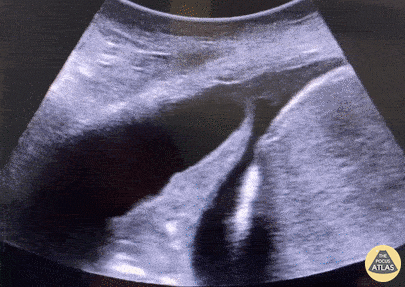

Accumulation de liquide entre les plèvres – pariétale et viscérale.

- Espace anéchogène ou hypoéchogène entre la base pulmonaire et le diaphragme.

- Signe de la colonne vertébrale visible au-dessus du diaphragme grâce à la conduction du son par le liquide.

- Poumon collabé flottant dans le liquide (« signe de la méduse »).

Caractère du liquide

- Anechogène : transsudat simple.

- Complexe ou cloisonné : exsudat ou empyème.

- Échogène : hémothorax.